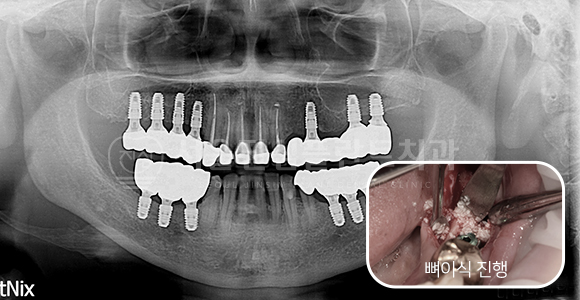

Ridge splitting + 뼈이식 임플란트

-

BEFORE

AFTER

하악 매우 좁은 골폭에 Ridge splitting + 뼈이식 상악동 거상술 + 뼈이식